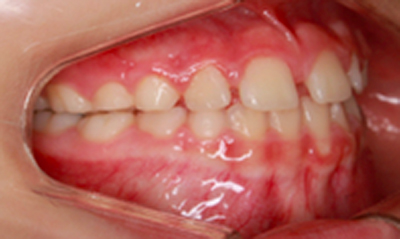

As imagens abaixo demonstram o mesmo caso de mordida cruzada anterior com fotografias intra orais laterais. Observe que os incisivos superiores, que se encontravam inicialmente atrás dos incisivos inferiores, passou a ocluir corretamente.